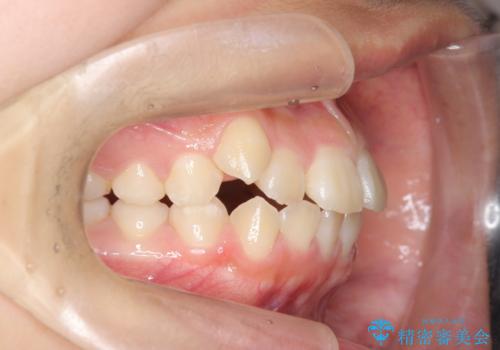

- 前歯の噛み合わせの開きの改善を求めて来院されました。

奥歯はほとんど動かさず(奥歯の噛み合わせはほとんど変えず)前歯のIPR矯正でガタつき前突感(出っ歯感)の改善を計画します。

ほとんど前歯のみの矯正治療であることからトータル14枚のマウスピースで並べるインビザラインライトによる治療を行います。